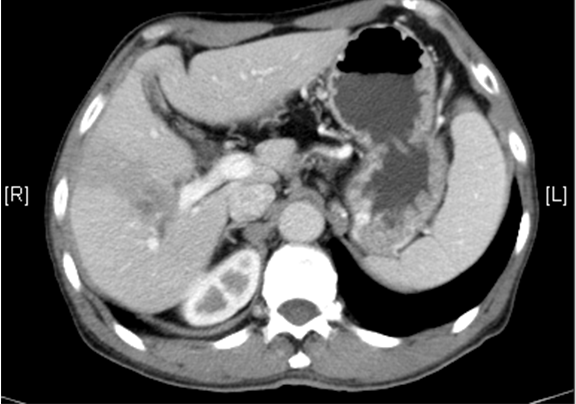

上腹部动态增强CT:1. 肝右叶占位性病变,考虑肝Ca 并肝右静脉瘤栓可能性大,请结合临床2. 副脾3. 肝内外胆管扩张,必要时MRCP检查4. 胰腺颈部小囊状低密度影,建议MRI 检查

通过调节窗宽窗位调整CT序号,对肿瘤,肝实质,胆囊,下腔静脉,肿瘤,肝动脉、门静脉及肝静脉等进行三维重建;系统自动计算肿瘤体积和肝脏体积。

模拟手术操作,自动计算切除肿瘤体积。肝脏体积为1058ml,肿瘤体积为562.1ml,肿瘤体积为肝脏体积的53.1%,通过比对60-70岁正常肝脏体积为1262.7±284.31 ml,通过术前模拟手术,精准判断切除后剩余肝脏体积能耐受,避免肝衰竭发生。

术前CT检查:

动脉期

静脉期

平衡期